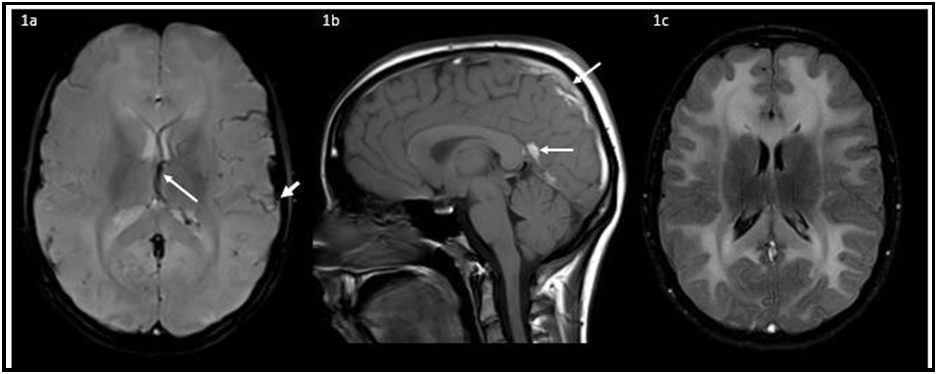

Reversible leukoencephalopathy and venous thrombosis in classical homocystinuria